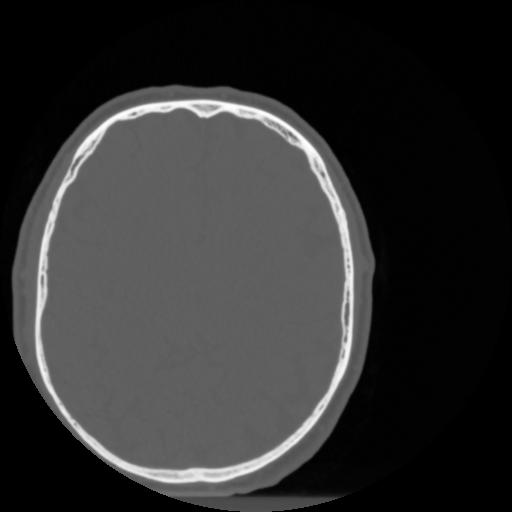

4 CEREBRO,,Vol,0.5,CEREBRO,,